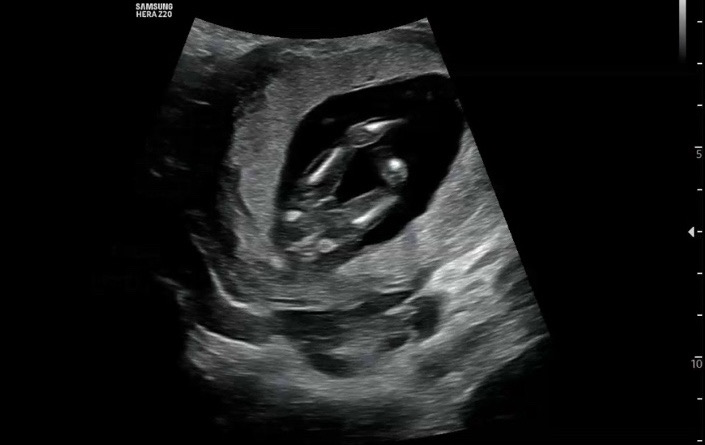

둘째인데 성별 한번 봐주세요ㅜㅜ

둘째인데 경험자들이 많으시니 성별 한번만 봐주세용 🥹